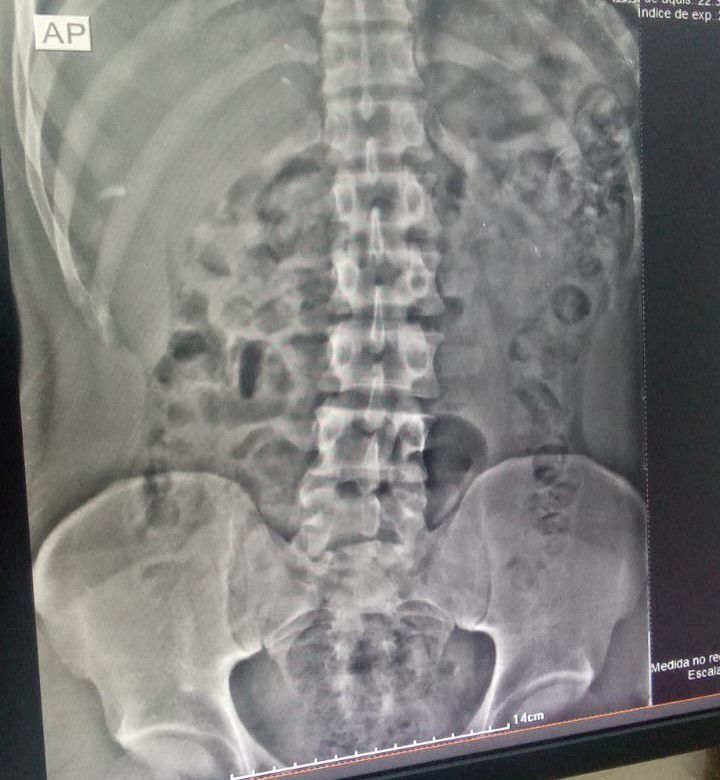

Um mecânico, de 24 anos, tentou entrar na Casa de Prisão Provisória de Formosa (CPP de Formosa), no Entorno do Distrito Federal, com 94 cápsulas de maconha dentro do estômago (110 gramas), na noite de quinta-feira (04/07). O homem foi flagrado pelo equipamento de scanner corporal, utilizado pelos servidores penitenciários no momento em que ele dava entrada no presídio.

“Durante sua entrada na CPP de Formosa, suspeitamos que havia algo errado. Na passagem pelo body scanner, vimos as substâncias ilícitas. Por isso, levamos o preso ao Hospital Regional de Formosa. A tomografia computadorizada sanou nossas dúvidas. Ele passou a madrugada expelindo as cápsulas dentro da cela, separado dos demais apenados”, explica o coordenador da 8ª Regional da Polícia Penal, Ayle Barbosa dos Reis Balbino.